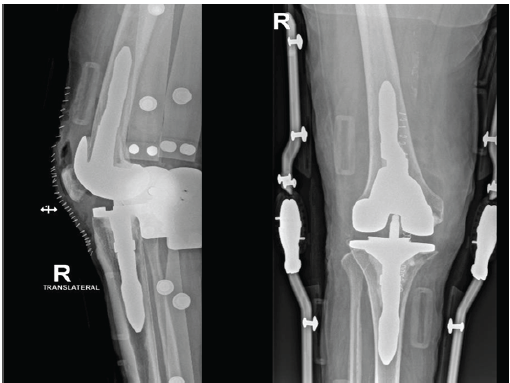

Postoperatively, he developed fever, abdominal pain, and diarrhea then later diagnosed as having Pseudomonas colitis induced by C difficile, attributed to long-term broad-spectrum antibiotic exposure. Managed by modifying his regimen to oral vancomycin, levofloxacin, and linezolid after infectious disease consultation. Despite systemic complications, the right knee remained stable, with preserved extension and flexion up to 90°. After stabilization, he underwent second-stage complex revision TKA (Fig. 6).

Figure 6. Right knee after second-stage revision total knee arthroplasty. Anteroposterior and lateral radiographs demonstrating successful second-stage revision with stemmed prosthetic components following eradication of infection.

Intraoperatively, the surgical field was clean, and the spacer was removed with minimal bone loss. Copious lavage was performed. Definitive components (Johnson and Johnson Attune system, femur size 5, tibia size 4 with stem, liner 5×7) were implanted. The medial and lateral collateral ligaments were stable, no patellofemoral maltracking was observed, and the intraoperative range was full extension and flexion up to 120°. Closure was completed in layers, and the distal neurovascular status was intact. Postoperatively, his vital signs were stable, pain was controlled, and the diarrhea gradually improved. He was discharged with a multidisciplinary home health plan, including orthopedic follow-up, weekly laboratories, and daily physiotherapy (Table 1).